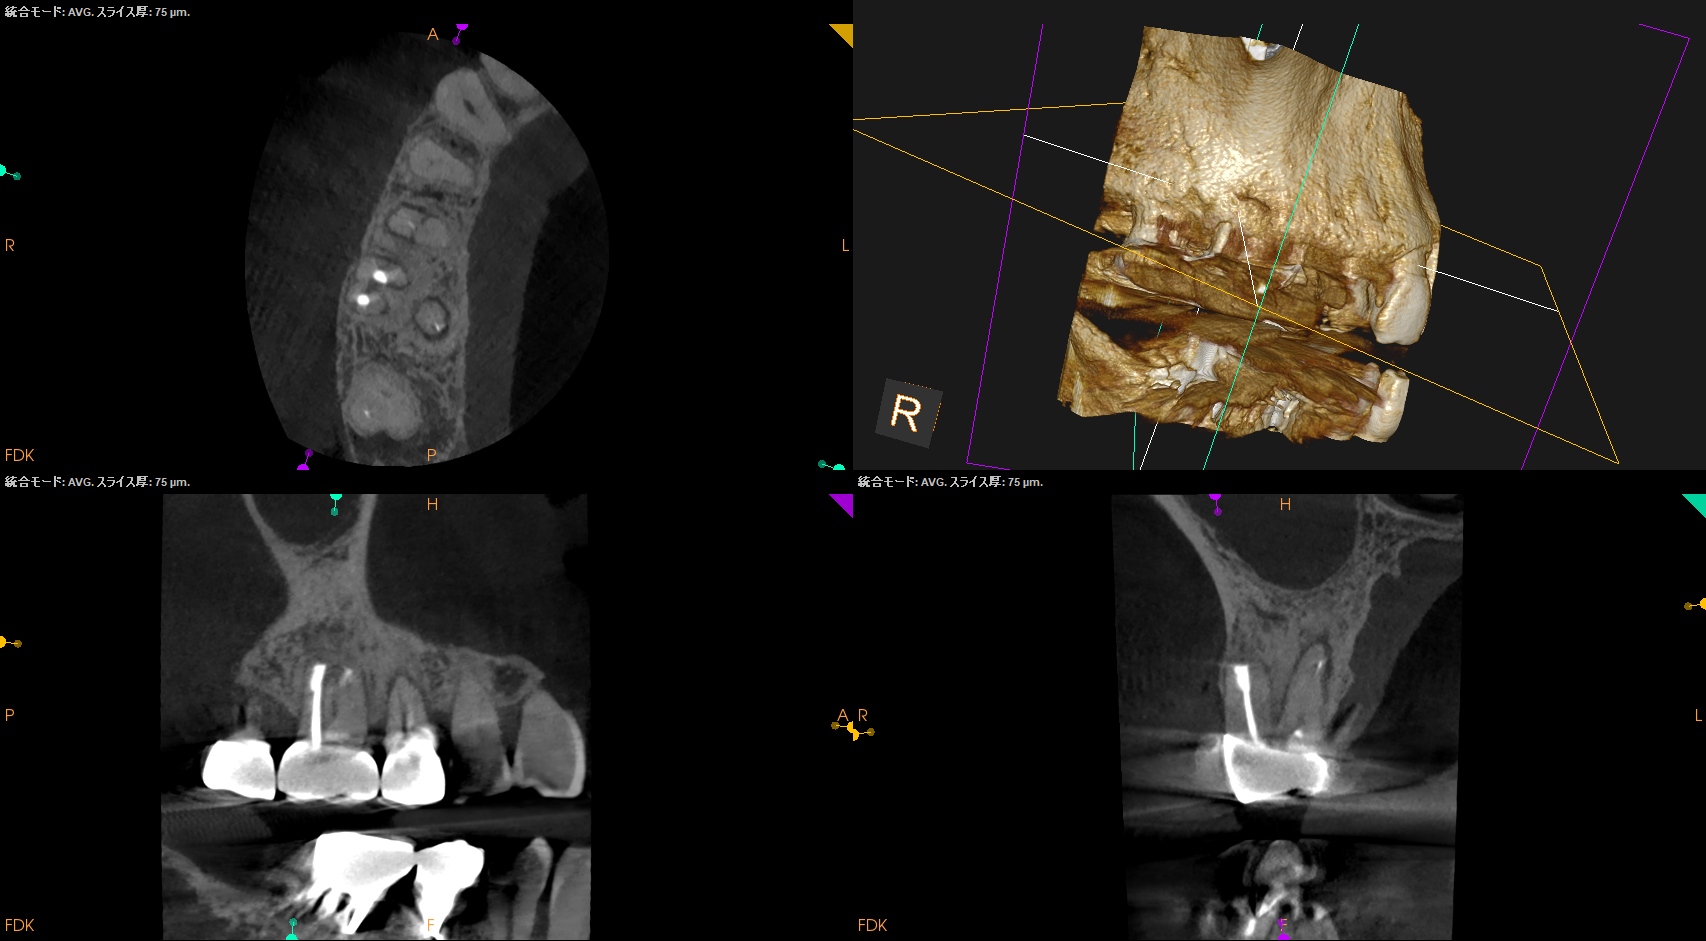

Pre-op CBCT(2024.11.25)

MB

DB

P

B

P根以外のMB,DBには根尖病変がありSinus tractがある。

ということは…

MB+DB Apicoectomyだ。